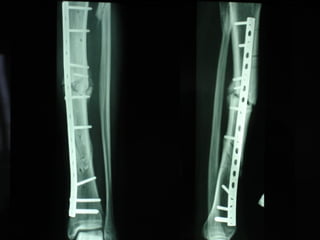

Dal Gennaio 2000 al Febbraio 2006 abbiamo trattato 167 fratture chiuse  con placca percutanea  in 164 pazienti :  27 lesioni diafisarie di gamba, 12 piloni tibiali ,  11 fratture prossimali di tibia, 36 fratture sovracondiloidee di femore, 17 fratture diafisarie di femore, 43 fratture metaepifisarie prossimali di omero, 21 diafisarie d’omero.  156 guarigioni 8 fallimenti

I buoni risultati ottenuti dipendono da 5 punti fondamentali:   una accurata riduzione percutanea della frattura  precise vie di accesso  l’utilizzo della placca che consenta il più lungo braccio di leva possibile il pretensionamento della placca  una sintesi con un ridotto numero di viti

Placche lunghe e pretensionate

Placche lunghe e pretensionate Sintesi con un ridotto numero di viti

VANTAGGI CHIRURGIA MININVASIVA Mini Open Inserimento della placca sottocutaneo per scivolamento Viti percutanee Preservazione dei tessuti molli Ridotto danno vascolare Rapida ripresa funzionale

Conclusioni Riduzione  anatomica Minimo trauma chirurgico Corretto equilibrio fra elasticità e stabilità Precoce mobilizzazione